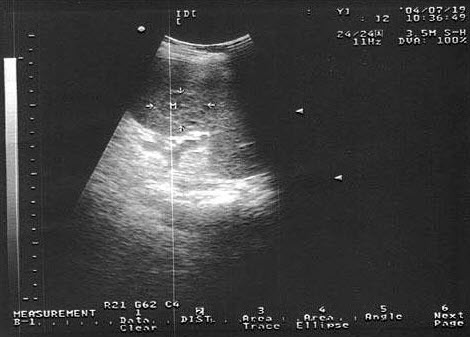

89、单项选择题

根据超声图像所示,判断致病人肾脏积水的梗阻在输尿管哪一段()

A.下段

B.中段

C.上段

D.膀胱内

E.肾盂内